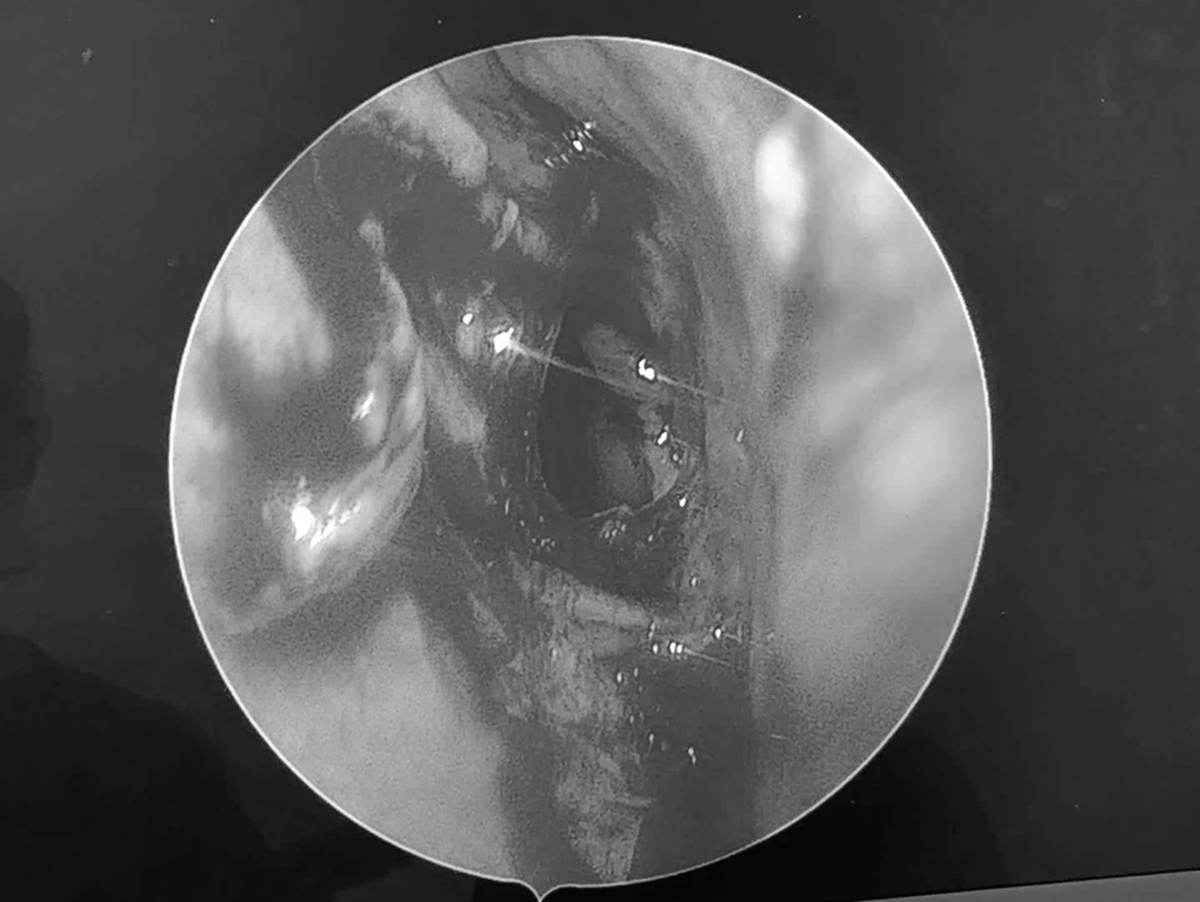

Sau khi thăm khám, bác sĩ Nguyễn Thanh Tiên cùng ê kíp đã tiến hành phẫu thuật mở xoang bướm và lấy sạch bệnh tích, dẫn lưu bằng phương pháp nội soi mũi xoang.